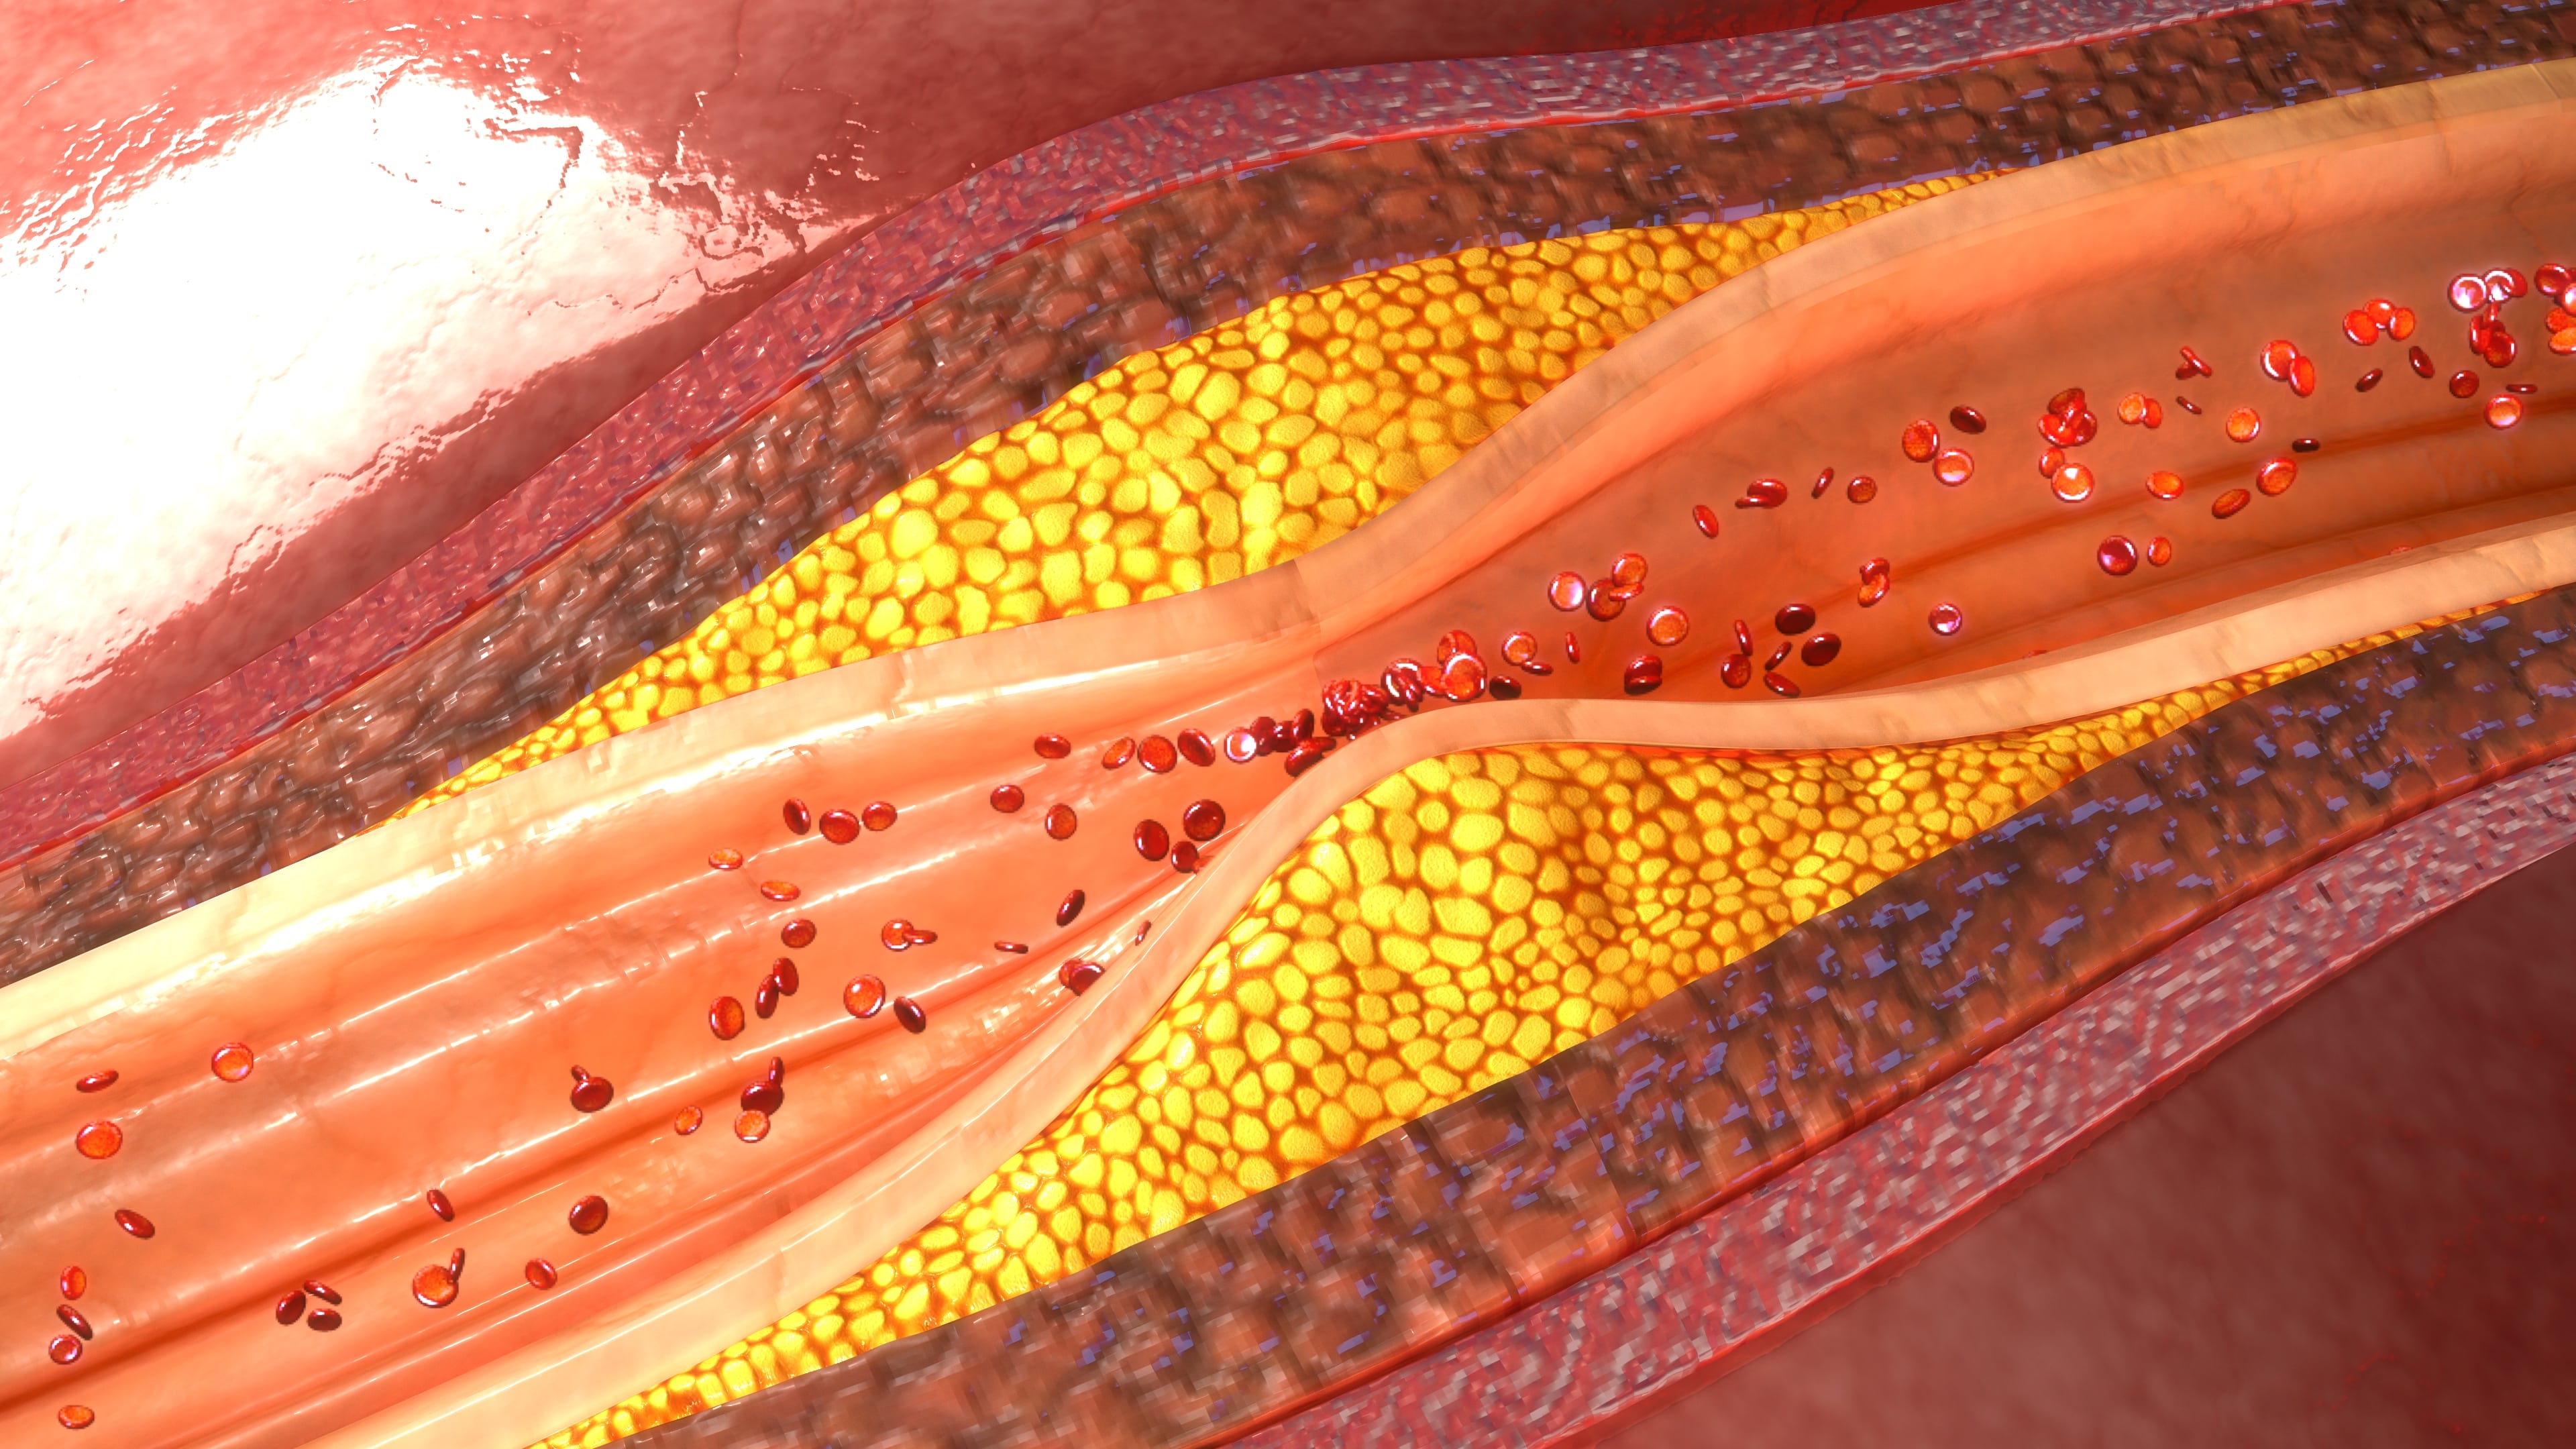

Irregular Sleep Patterns Associated with High Cholesterol, Diabetes, and Other Metabolic Disorders

A new study shows how important a good night’s sleep is for the prevention of high cholesterol, diabetes, and other metabolic disorders. In fact, it was found that every hour of variability in sleep timing could lead to a 27 percent greater risk of a metabolic abnormality. Funded by the National Heart, Lung, and Blood ...click here to read more